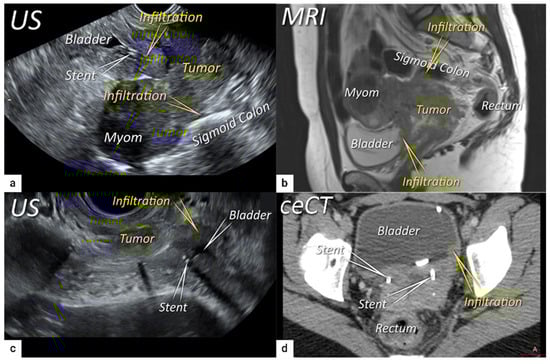

3.3. Extrauterine Extension (Vagina, Parametria, Pelvic Side Wall, Hydronephrosis and Others)

3.4. Extension to Surrounding Organs (Bladder, Rectum, Sigmoid Colon)

| T4 f | IVA f | Tumour invasion into the mucosa of the bladder or rectum (biopsy-proven) or into adjacent organs. | Tumour invasion into the mucosa of the bladder or rectum on imaging, confirmed by biopsy. US: Negative sliding sign, hypoechogenic tumour infiltration of bladder/rectal wall up to echogenic mucosa with polypoid tumour seen intraluminally. MRI: Focal or diffuse disruption of the normal T2-low signal intensity wall of the bladder/rectum, irregular or nodular wall, sometimes including an intraluminal tumour mass. Bulous edema sign, which is hyperintense thickening of the bladder mucosa on T2W images, is only an indirect sign of invasion and should not be regarded as T4 unless confirmed mucosal infiltration at cystoscopy. Infiltration of the posterior bladder wall without mucosal infiltration should not be regarded as T4a. |